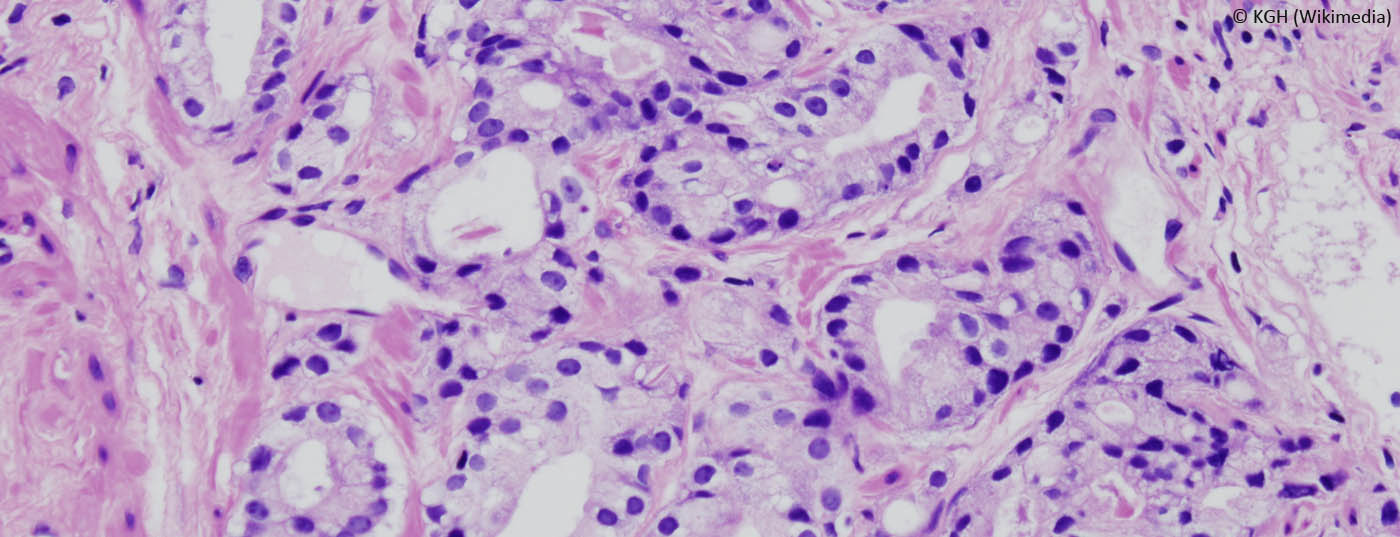

prostatakrebs_histo2

Aktive Überwachung beim Prostata­karzinom – wann ist dies möglich?

Die Früherkennungsmöglichkeiten des Prostatakarzinoms (PCa) wurden mit Einführung des PSA (Prostata-spezifisches Antigen) revolutioniert. Seit der Einführung fiel allerdings auf, dass eine grosse Zahl Männer mit einem Niedrig-Risiko-Prostatakarzinom mit anstatt an ihrem Karzinom versterben. Um diese sogenannten Überdiagnosen nicht zusätzlich einer Übertherapie auszusetzen, wurde in einem Vortrag des 7. Interdisziplinären Prostatakarzinomsymposium in St. Gallen die Möglichkeit der aktiven Überwachung erläutert.